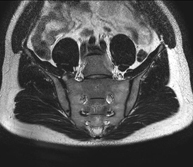

Prueba diagnóstica no invasiva que consiste en la obtención de imágenes de alta definición anatómica de la pelvis mediante el empleo de un campo electromagnético y ondas de radio (con un emisor y un receptor). No utiliza radiación ionizante. Se realiza para estudiar patologías del útero, del ovario, de las trompas y la vagina, ya sean de origen tumoral, inflamatorio o vasculares. Además permite valorar les estructuras adyacentes localizadas en la pelvis, identificando sus alteraciones. A veces requiere el uso de contraste intravenoso (Gadolinio) para caracterizar las lesiones. - RM Pelvis masculina